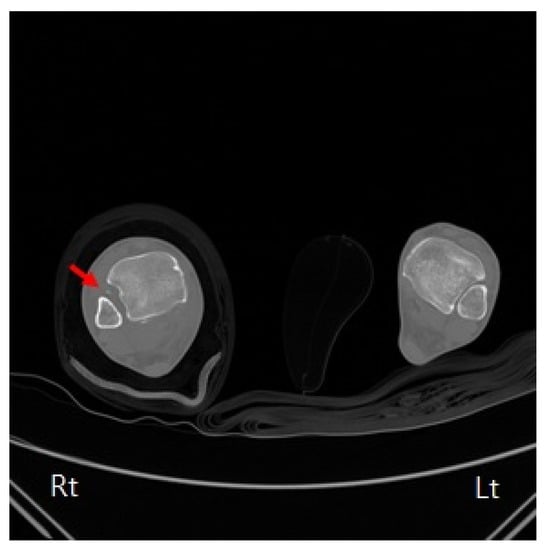

2. Case Presentation